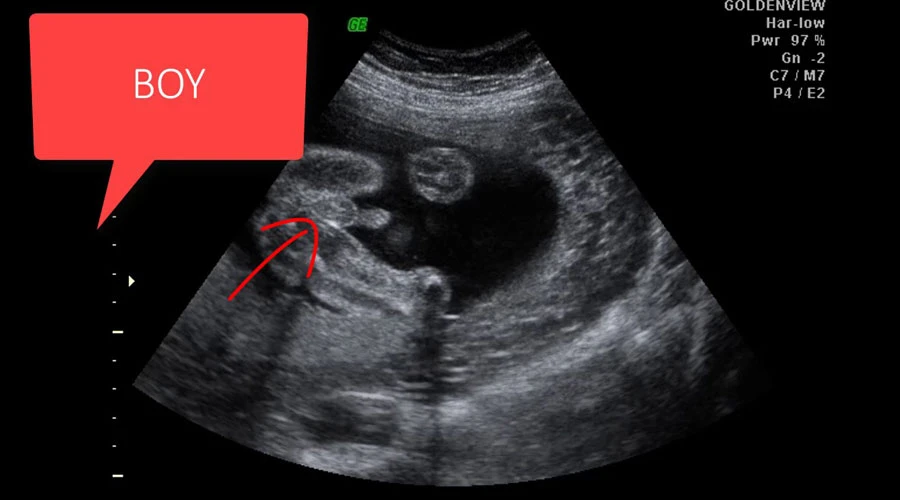

Hamileliğin 13.haftasına girilmesiyle beraber anne adayları bebeğinin cinsiyetini öğrenmek için sabırsızlanıyor, ultrasonda bebeklerinin nasıl göründüğünü merak ediyor. İşte 13 haftalık bebek ultrason görüntüleri:

13 HAFTALIK HAMİLELİKTE BEBEĞİN ULTRASONLA CİNSİYET GÖRÜNTÜLERİ

Bebeğin ilk ultrason görüntülerini görmek, kalp sesini duymak çok heyecan ve mutluluk verici. Anne baba olmaya hazırlanan çoğu çift bebeklerinin ultrasondaki fotoğraflarını gördüklerinde gözyaşlarına hakim olamayıp sevinçten ağlıyor, bu durumu sevdikleriyle paylaşıyor. Artık çoğu kişi internet üzerinden ultrason fotoğraflarını yayımlayıp sevinçlerini adeta tüm dünyaya haykırıyor. İşte 13 haftalık hamilelikte bebeklerin ultrason fotoğrafları:

13 haftalık hamilelikte ultrason yoluyla cinsiyet belirlenebilir. Ancak 13.haftada cinsiyetin tespit edilmesinde hata payı vardır. 13. Haftada ultrasonda kız olup da daha sonraki ultrason testlerinde erkek gözüken bebek olduğu gibi bunun tam tersi durumlar da yaşanabiliyor. Bebeğin cinsiyetinin kesin olarak söylenebilmesi için 16. hamilelik haftasını beklemek gerekiyor.

Araştırmalar 13 haftada cinsiyet tahmini doğruluk oranının %98,3 olduğunu gösteriyor. Yani 13 haftalık hamilelikte yapılan ultrason bebeğin cinsiyetini kesine yakın belirleyebiliyor. Hamileliğin 13. Haftasında ultrason testinin yanlış çıkma oranı ise %1,7.

Acta Obstetricia et Gynecologica Scandinavica Tıp Dergisi’nde Ocak 2008’de yayımlanan makalede hamileliğin ilk üç ayında olan 496 kadın üzerinde yapılan araştırmada, fetal cinsiyeti doğru bir şekilde belirlemedeki başarı oranının gebelik haftasıyla birlikte arttığı görüldü. 11 haftalık hamile kadınların %71,9’sı, 12 haftalık hamilelerin %92’si ve 13 haftada hamilelerin ise %98,3’ünün cinsiyeti kesin olarak tespit edildi.